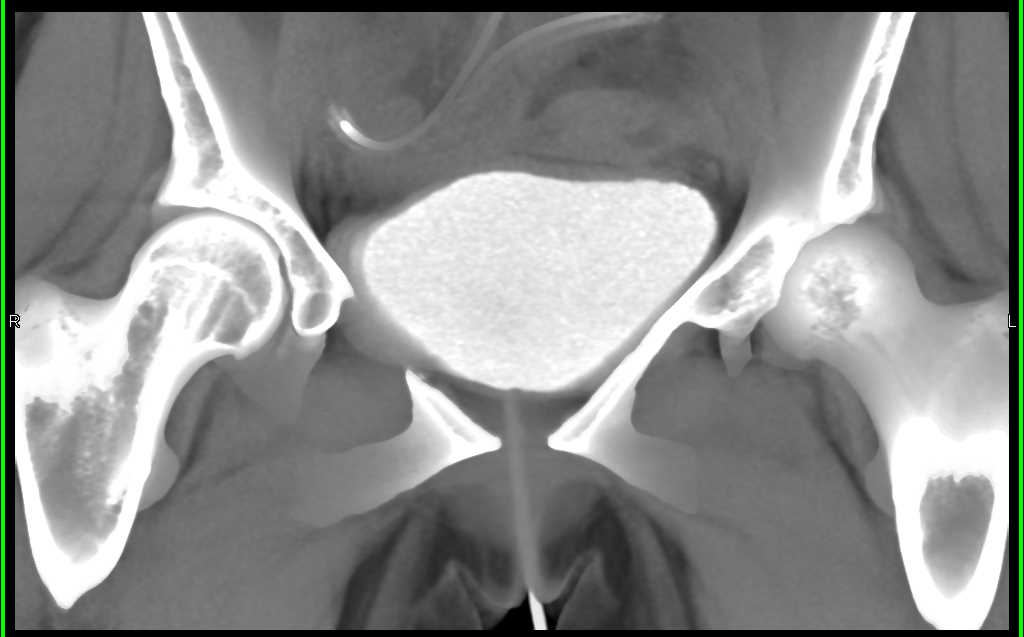

Extravasation from the Bladder